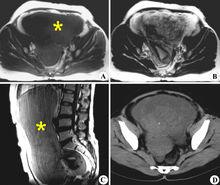

垂體泌乳素瘤是最常見的垂體瘤,多發於生育期婦女,是導致女性不孕的重要原因之一。該腫瘤雖屬良性,但能高功能分泌PRL,引起患者血清PRL升高。高水平的PRL可抑制下丘腦促性腺激素釋放激素的合成與釋放,因而LH與FSH水平降低,無脈衝型分泌,卵泡發育障礙。同時,PRL升高還可直接影響卵巢甾體激素合成能力,導致雌、孕激素不足,因而患者出現月經稀少或閉經、不孕。糖尿病患者也會導致不孕。

內分泌不孕多囊卵巢綜合症(polycystic ovary syndrome, PCOS)是生育年齡婦女常見的一種複雜的內分泌及代謝異常所致的疾病,是最常見的婦女內分泌紊亂疾病之一。其特徵為多毛,無排卵與肥胖,並對生殖有很大影響。